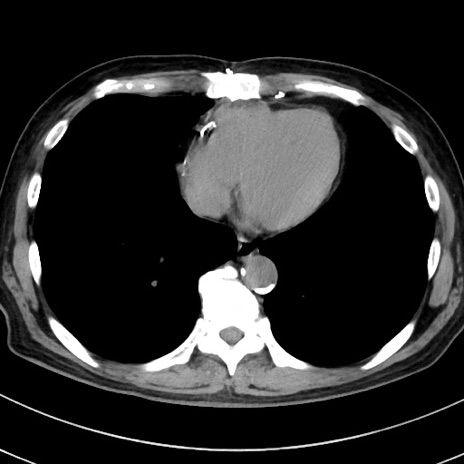

症例38(横断像)

【症例】70歳代 男性

【主訴】腹痛・嘔吐

【現病歴】昨晩より、嘔吐・腹痛あり。今朝になっても嘔吐あり。来院。

【既往歴】心臓バイパス手術、開腹胆摘、腸閉塞

【身体所見】BP 107/71mmHg、HR 116/min、腹部:平坦、軟、下腹部に軽度圧痛あり。反跳痛なし。

【データ】WBC 15100、CRP 0.32